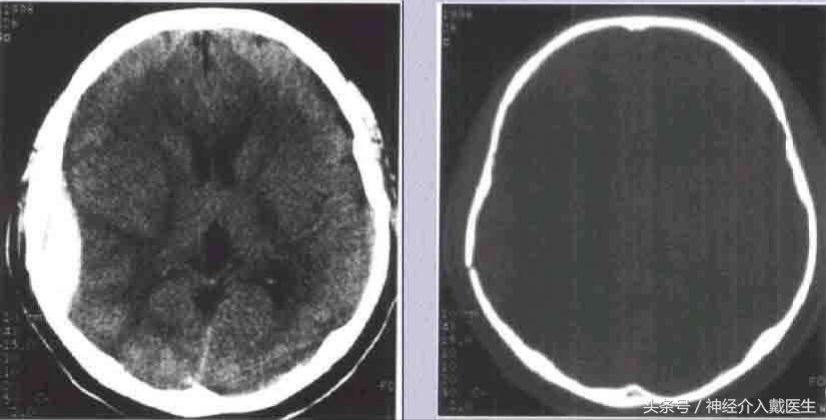

儿童生长性骨折:好发于额顶部,为小儿颅盖线形骨折中的特殊类型,婴幼儿多见。一般认为小儿硬脑膜较薄且与颅骨内板贴附较紧,当颅骨发生骨折裂缝较宽时,硬脑膜亦常同时撕裂、分离,以致局部脑组织、软脑膜及蛛网膜突向骨折的裂隙。由于脑搏动的长期不断冲击,使骨折裂缝逐渐加宽,以致脑组织继续突出,最终形成局部搏动性囊性脑膨出,病儿常伴发癫痛或局限性神经废损。治疗原则以早期手术修补硬脑膜缺损为妥。 凹陷骨折多见于额、顶部,常为接触面较小的钝器打击或头颅碰撞在凸出的物体上所致。着力点头皮往往有擦伤、挫伤或挫裂伤。颅骨大多全层陷入颅内,偶尔仅为内板破裂下凹。一般单纯凹陷骨折,头皮完整,不伴有脑损伤多为闭合性损伤,但粉碎凹陷骨折则常伴有硬脑膜和脑组织损伤,甚至引起颅内出血。

( 1 )闭合性凹陷骨折 儿童较多,尤其是婴幼儿颅骨弹性较好,钝性的致伤物,可引起颅骨凹陷,但头皮完整无损,类似乒乓球样凹陷,亦元明显的骨折线可见。患儿多无神经机能障碍,无需手术治疗。如果凹陷区较大较深,或有脑受压症状和体征时,可于凹陷旁钻孔,小心经硬膜外放入骨撬,将陷入之骨片撬起复位。术后应密切观察以防出血。

成年人单纯凹陷骨折,如果面积大于 5cm,或者直径,深度超过 lcm ,或者伴有神经缺损症状和体征,需要手术治疗。